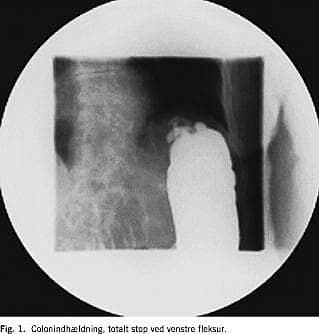

En 87-årig kvinde med kendt tidligere transitorisk cerebral iskæmi og velbehandlet myksødem blev henvist af egen læge til koloskopi pga. ca. et år varende tendens til træg afføring og anæmi. Ved koloskopien fandt man ca. 90 cm fra anus en malignt udseende stenotisk proces. En colonindhældning viste totalt stop ved venstre fleksur ( Fig. 1 ), supplerende undersøgelser viste ingen tegn på metastaser. Der blev anlagt selvekspanderende metalstent under gennemlysning. Der var umiddelbart efter proceduren luft- og fæcesafgang, og en kontrolrøntgen viste velekspanderet stent i det stenotiske colonsegment (Fig. 2 ). Seks dage efter blev der foretaget elektiv laparoskopisk venstresidig hemikolektomi og primær anastomose. Man fandt en tumor i venstre fleksur. Det postoperative forløb var ukompliceret, og patienten kunne udskrives i velbefindende og med tarmfunktion den syvende postoperative dag. En histologisk undersøgelse viste Dukes C adenokarcinom. En kontrolkoloskopi for clean colon viste normale forhold. Ved klinisk kontrol efter et år var patienten velbefindende, uden tegn på recidiv eller metastaser.